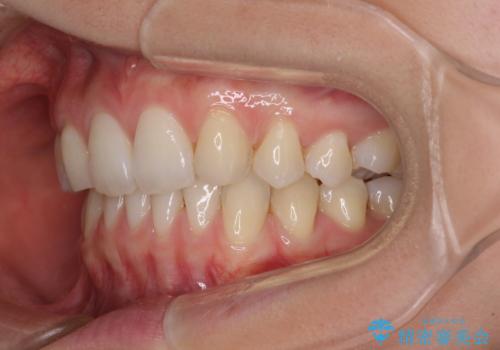

上顎前歯が2本欠損 インビザラインによる叢生の解消

- 深い咬み合わせと前歯のデコボコを気にして来院された患者様です。

上顎前歯2本が欠損しているため、妥協的なゴールを設定しインビザラインで矯正治療を行うこととしました。

上下前歯の大きさのアンバランスにより、深い咬み合わせと奥歯の咬みにくさがなかなか解決されず、治療に長期間を要することとなりました。